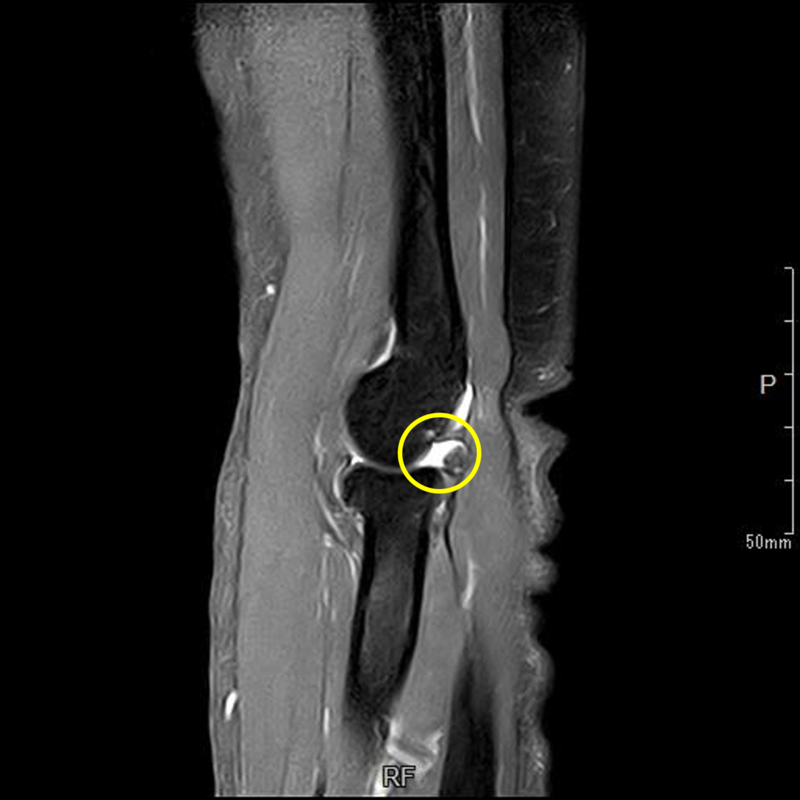

肘の離断性骨軟骨炎(以下:OCD:osteochondritis dissecans)は上腕骨小頭という部位に好発することが多いです。

OCDは成長期の代表的なスポーツ障害であり、野球などといった投球・投擲動作を行うスポーツ選手で投球側に発生することが多いです。大半は10-12歳で発症し成長期における有病率は2-3%と頻度は少ないが進行するとスポーツにみならず、日常生活お支障をきたすことが多い怪我です。そのため、早期発見・早期治療が重要となります。

OCDを発見するにはレントゲンや超音波検査で上腕骨小頭軟骨下骨の状態を観察します。

軟骨下骨の不整像が軽微か不明の場合はMRI検査を行いOCDの確定診断を行います。

12歳・男性・スポーツは野球(週2回/4年間)

2024年3月頃から外傷誘因なく疼痛出現。

2024年4月上旬、他院受診して超音波検査で軟骨が剝がれていると診断を受けたが経過観察のみ。

2024年5月、当院受診。レントゲン撮影をして離断性骨軟骨炎と診断されてリハビリ開始。

リハビリでは、徒手療法(マッサージ)・運動療法(筋力トレーニング ストレッチ)・物理療法を実施していましたが、

疼痛消失には至らず、組織修復を目的に体外衝撃波を実施しました。

体外衝撃波(拡散型圧力波治療)は、週1回の頻度で3回実施しました。

現在は、リハビリテーションでトレーニング継続中です。